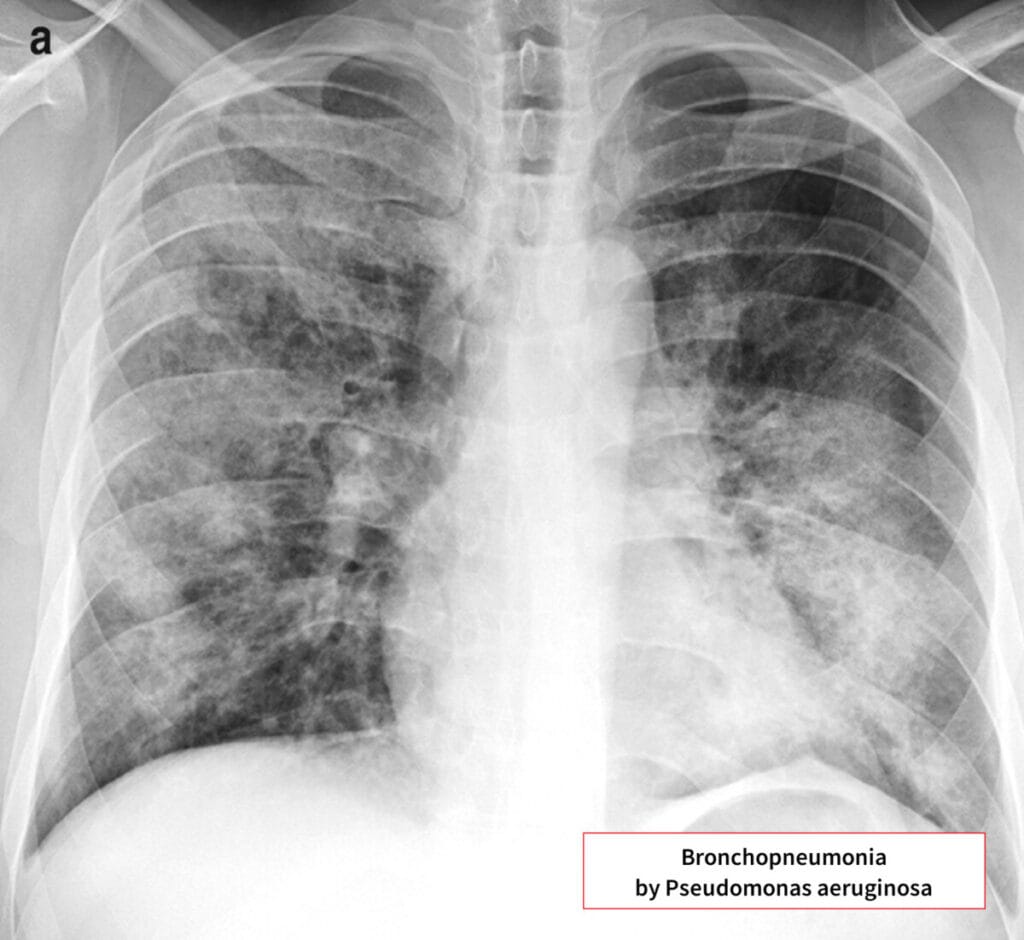

🟦 폐렴 (병원성/기회감염) |

기침, 호흡곤란, 녹색 가래. 인공호흡기 관련 폐렴(VAP)에서 가장 흔한 원인균 중 하나. |